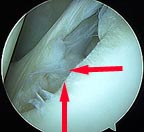

Bankart lesion